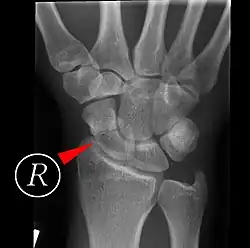

Fracture

Fractures of the scaphoid are the most common of the carpal bone injuries, because of its connections with the two rows of carpal bones.[1]: 177

The scaphoid can be slow to heal because of the limited circulation to the bone. Fractures of the scaphoid must be recognized and treated quickly, as prompt treatment by immobilization or surgical fixation increases the likelihood of the bone healing in anatomic alignment, thus avoiding mal-union or non-union.[6] Delays may compromise healing. Failure of the fracture to heal ("non-union") will lead to post-traumatic osteoarthritis of the carpus.[1]: 189 One reason for this is because of the "tenuous" blood supply to the proximal segment.[3] Even rapidly immobilized fractures may require surgical treatment, including use of a headless compression screw such as the Herbert screw to bind the two halves together.

Healing of the fracture with a non-anatomic deformity (frequently, a volar flexed "humpback") can also lead to post-traumatic arthritis. Non-unions can result in loss of blood supply to the proximal pole, which can result in avascular necrosis of the proximal segment.

Scaphoid fractures may be difficult to diagnose via plain x-ray. A repeat x-ray may be required at a later date, as might cross-sectional imaging via MRI or CT scan.[6]